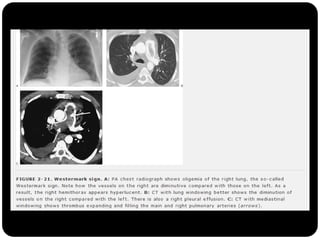

Sinal de Westermark

Sinal da corcova de Hampton